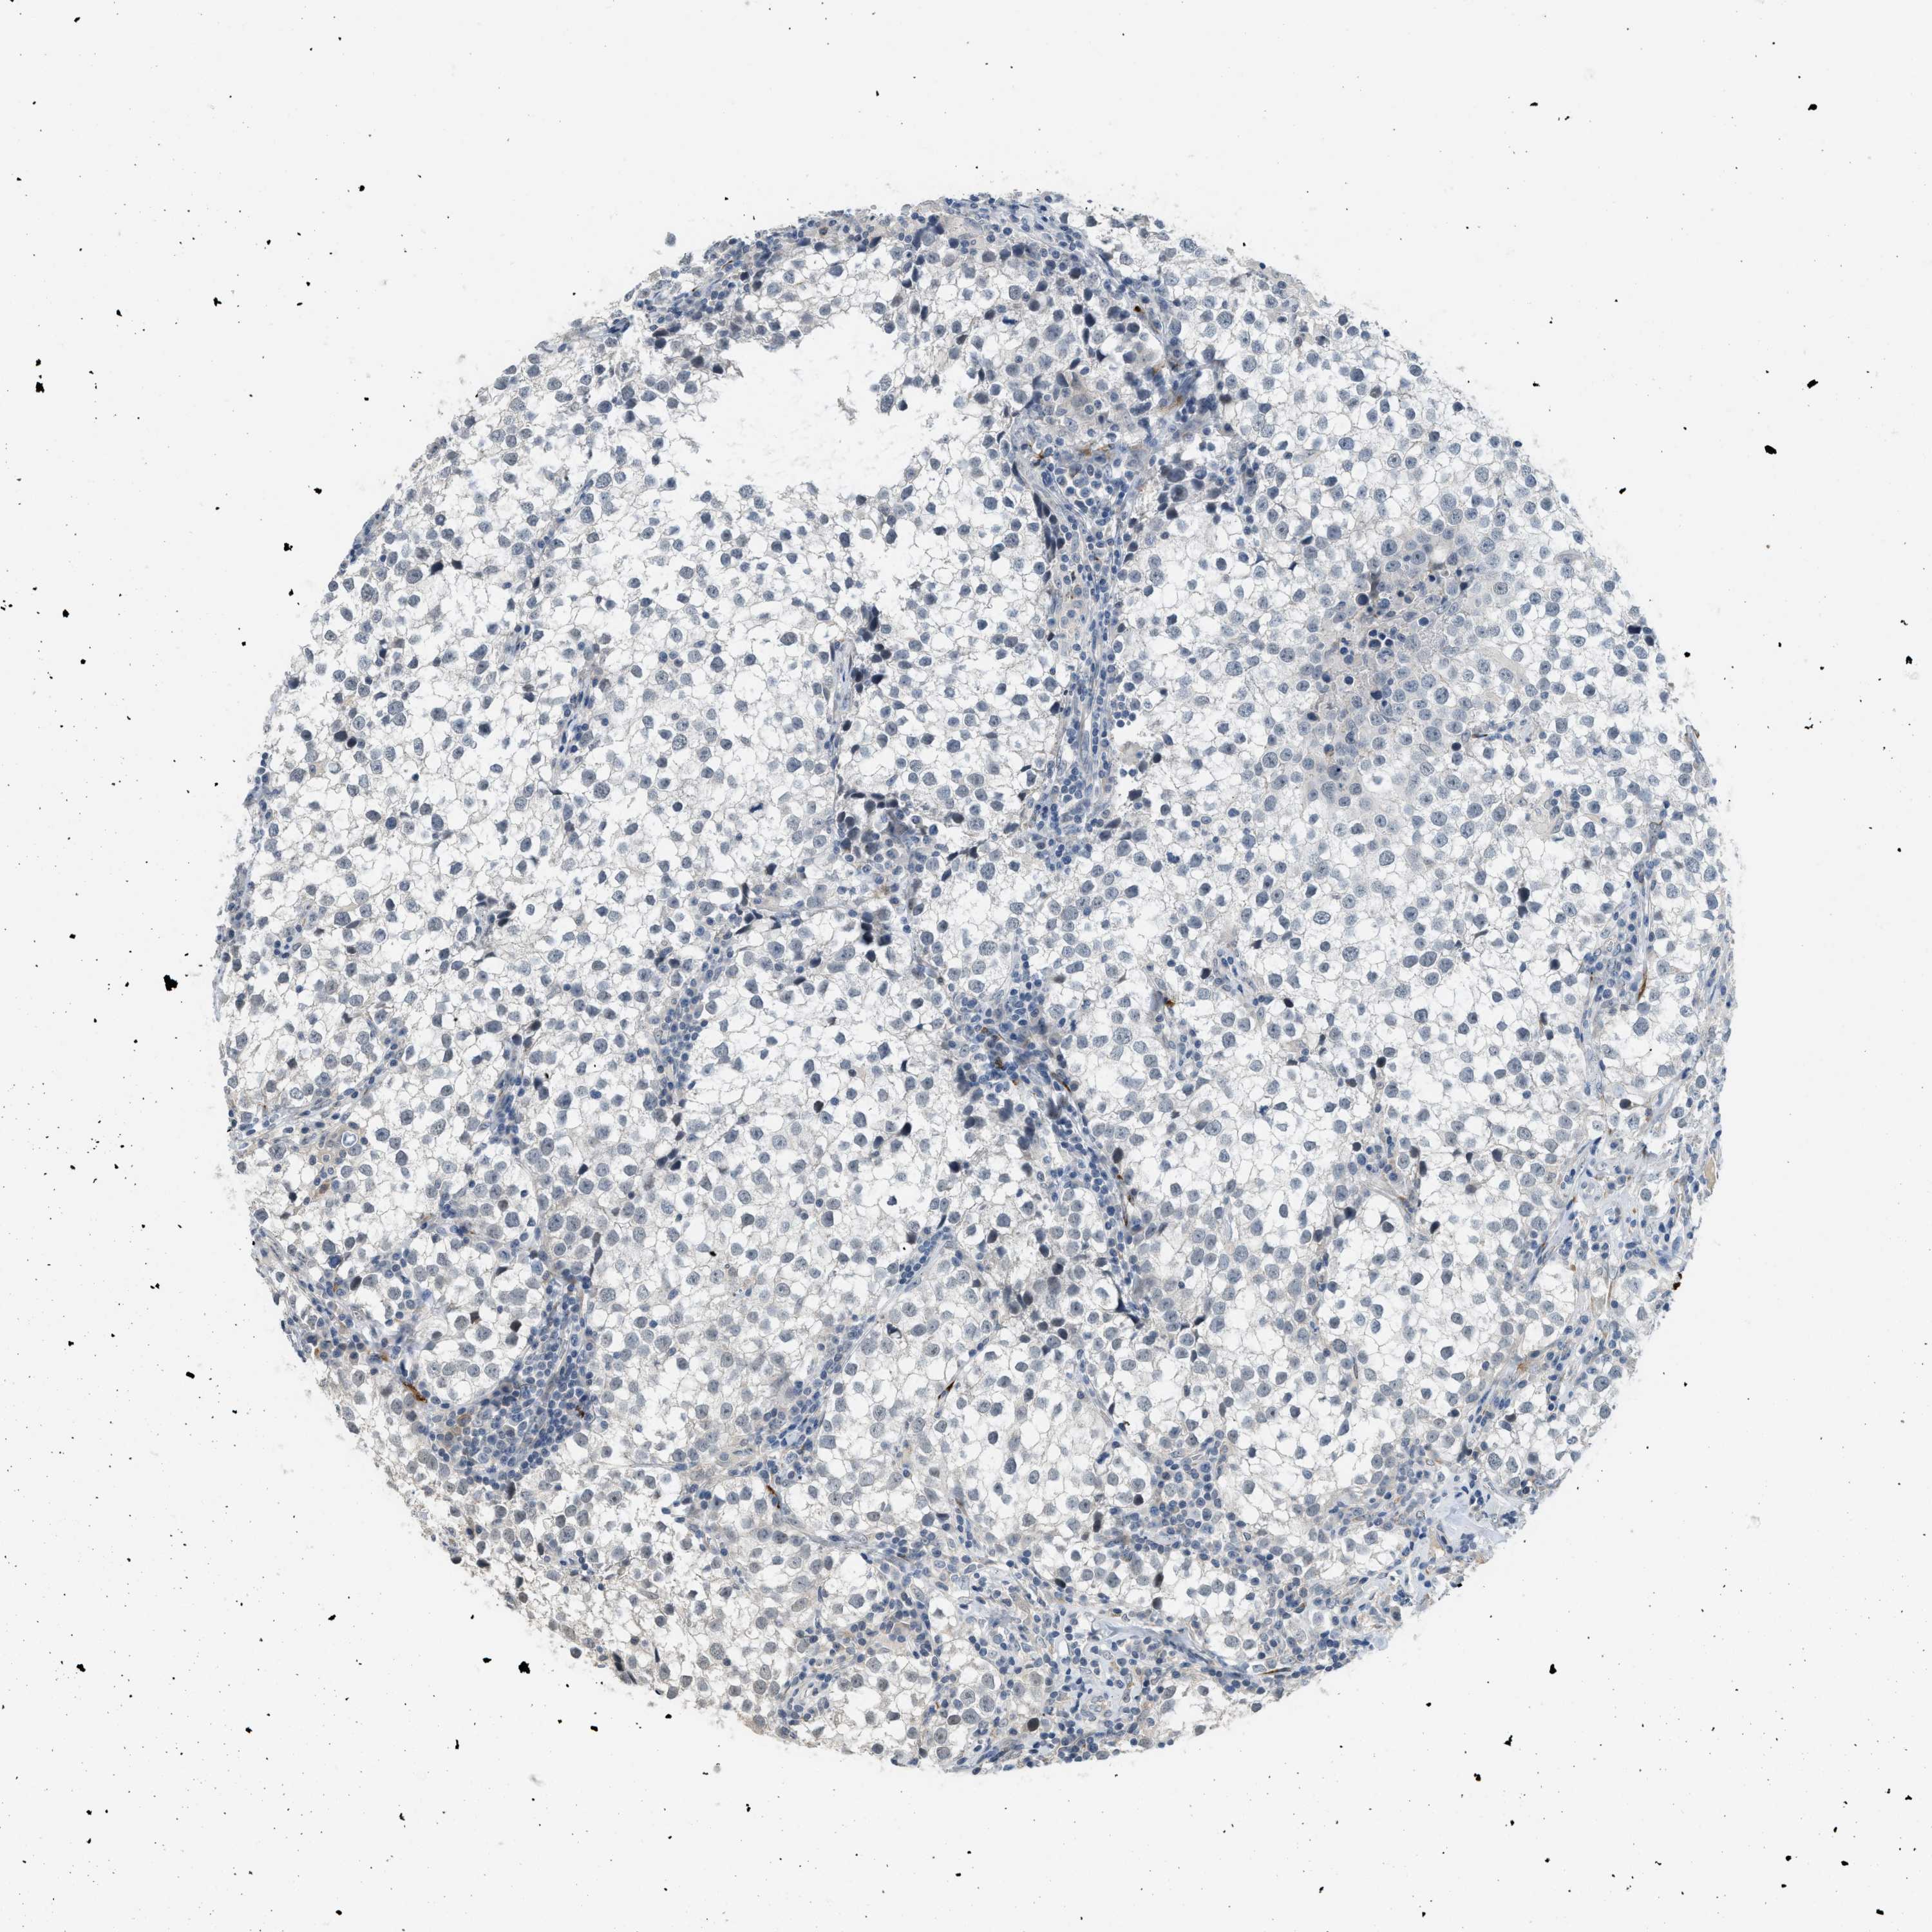

TESTIS CANCER - Protein expressioni

A mouse-over function shows sample information and annotation data. Click on an image to view it in a full screen mode. Samples can be filtered based on level of antibody staining by selecting one or several of the following categories: high, medium, low and not detected. The assay and annotation is described here.

Note that samples used for immunohistochemistry by the Human Protein Atlas do not correspond to samples in the TCGA dataset.

Antibody stainingi

Antibody staining in the annotated cell types in the current human tissue is reported as not detected, low, medium, or high, based on conventional immunohistochemistry profiling in selected tissues. This score is based on the combination of the staining intensity and fraction of stained cells.

Each image is clickable and will lead to virtual microscopy that enables deeper exploration of all samples and also displays staining intensity scores, fraction scores and subcellular localization as well as patient and tissue information for each sample.

Antibody HPA019184

Staining

High

Medium

Low

Not detected

Intensity

Strong

Moderate

Weak

Negative

Quantity

>75%

75%-25%

<25%

None

Location

Nuclear

Cytoplasmic/membranous

Cytoplasmic/membranous,nuclear

Carcinoma, Embryonal, NOS

Seminoma, NOS